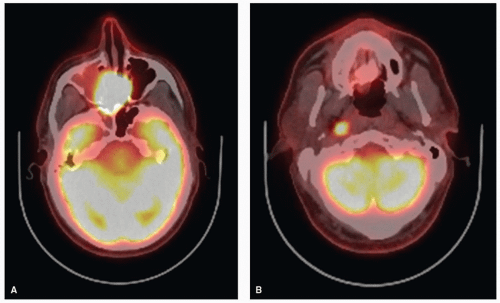

10.1016/j.canrad.2016.07.035 abstract the nasal cavity and parasinusal cancer are rare (10% of tumors of the head and neck) and are mainly represented by squamous cell carcinoma of the nasal cavity or the maxillary sinus and adenocarcinoma of the ethmoid sinus (occupational disease, wood dust). Nasal cavity (nose) and paranasal sinus cancer. Learn about the causes and risk factors for nasal cavity and paranasal sinus cancers and what you might be able to do to help lower your risk.

Tumors Of The Paranasal Sinuses Include Diverse Histologies With Variable Behaviors, Including Squamous Cell Carcinoma, Minor Salivary Gland Adenocarcinoma, Adenoid Cystic.